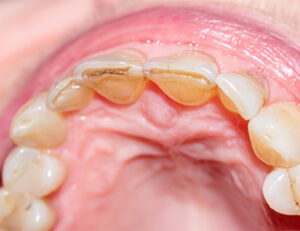

歯垢・歯石

歯の表面がザラザラする代表的な原因は、歯垢と歯石です。

歯垢は、口腔内の細菌が食べかすを栄養に増殖することで歯の表面に形成される、白っぽく粘着性のある膜です。

形成初期であれば歯ブラシによるブラッシングで除去できますが、放置すると唾液中のカルシウムやリン酸が沈着して硬くなり、歯石へと変化します。

歯石は歯垢より硬く、表面が粗いため、さらに強いざらつきとなり、歯垢の付着を促進します。

色は黄色や茶色、場合によっては黒っぽく、通常の歯磨きでは除去できません。

固くなった歯石は、歯科医院で専用の器具を使って除去する必要があります。